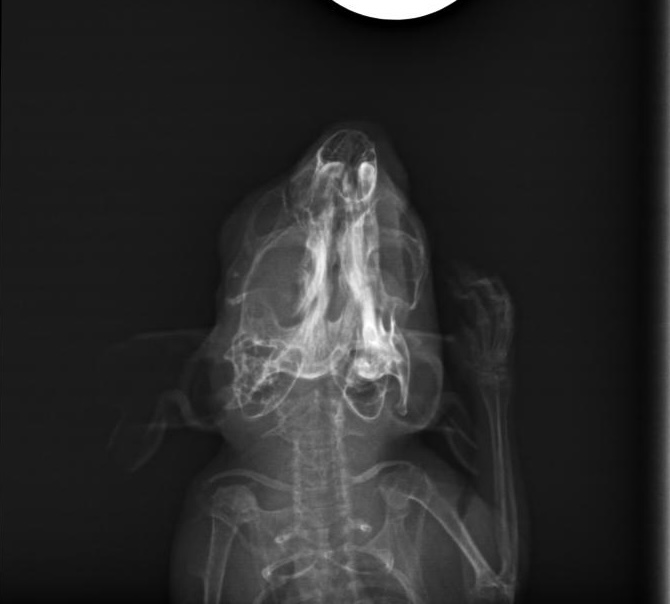

Also bin ich mit ihr am 15. Oktober zum Tierarzt gefahren und habe sie dort zusammen mit Freundin Leni abgegeben. Mit der Bitte die Zähne wirklich gut zu checken und auch ein Röntgenbild anzufertigen.

Mittags dann der Anruf: Klein Ida hat sich den Kiefer gebrochen. Mist, mist, mist! Tja nun... was ist hier die beste Lösung. Die Tierärztin und ich schweigen erst einmal... wägen ab. Doch wir sind uns einig, dass die kleine Maus eine Chance bekommen soll. Somit werden nur die vorderen Schneidezähne etwas gekürzt, da diese schon etwas zu lang waren und ansonsten bleibt uns nur die Versorgung mit Schmerzmittel und Brei.

Hier die Bilder, ich habe extra gefragt, ich darf sie teilen. Ich sehe darauf nix, aber ihr vielleicht